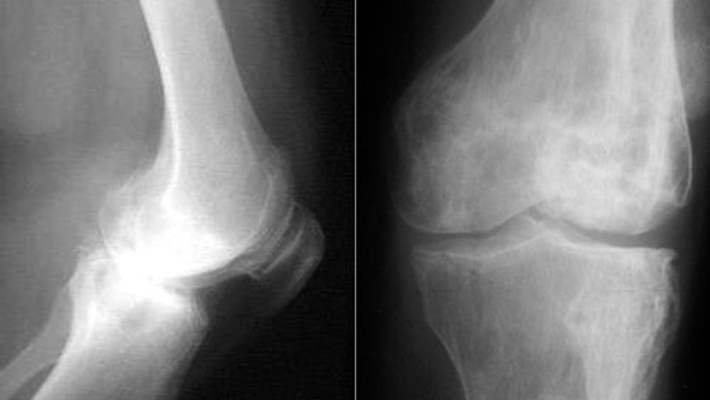

Makoplasti robotik parsiyel diz cerrahisi sistemini Türkiye'ye getiren Medicall Firması'nın genel müdürü Ayhan Öztürk, basın toplantısında yaptığı konuşmada, kıkırdakların tahrip olmasından kaynaklanan ve yaygın görülen osteoartritin merdiven inip çıkmayı, oturup kalkmayı olumsuz etkilediğini, hastalığın robotik diz cerrahisi yöntemiyle tedavi edilebildiğini kaydetti.

''Hastanın öncelikle tomografi görüntüsü çekiliyor. Bu görüntüden 3 boyutlu görüntü elde ediliyor. Cihaz özel yazılımı sayesinde sadece hasarlı kemik dokusunu gösteriyor. Diz kapağına yerleştirilecek implantlar 3 boyutlu görüntüde yerleştirilerek sanal olarak cerrahi planlanıyor. Bu, hekim tarafından onaylandıktan sonra robota yükleniyor. Sonrasında robotik kol sayesinde cerrah, işlemi plana uygun olarak gerçekleştiriyor. Sistemle hata minimuma indiriliyor.''

Cihazı ilk kez bu kongrede tanıttıklarını belirten Ayhan Öztürk, ''Cihaz, diz ameliyatı gereken hastalarda herhangi bir hataya meyil vermeksizin 3-4 santimlik bir kesiden robotik kolun içeri girerek oradaki sadece hasarlı dokunun alınmasını sağlıyor. Böylelikle travma minimuma indirilmiş oluyor. Hastanın kısa sürede ayağa kalkmasını sağlıyor. Hastanın 1-4 gün içinde ayağa kalkması ve fizik tedavi süreçlerinin ciddi olarak kısalması mümkün''diye konuştu.

Doral, ''Dizdeki hasarlı dokuyu robot alıyor, kıkırdağın olmadığı yere dışarıdan protez takılıyor. Ameliyatı robot yapıyor ama robotun arkasında insan var'' dedi.